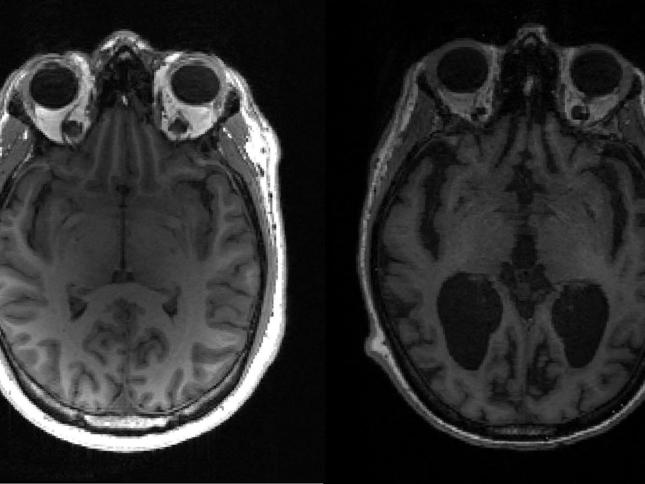

در بیماری آلزایمر تودههای سمی پروتئین بهتدریج و همزمان در چند ناحیه مغز شکل میگیرد